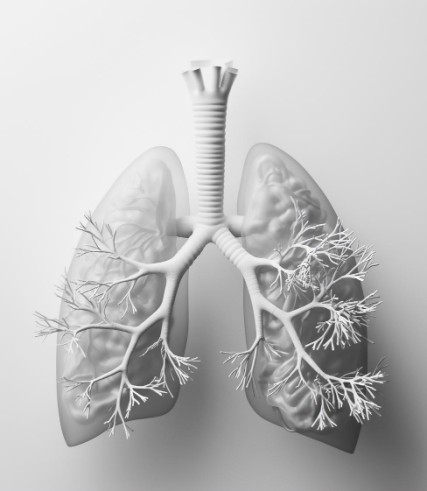

Spirometry

Our spirometry tests measure lung function, assisting in the diagnosis and management of respiratory conditions like asthma, COPD, and other lung-related issues.

COPD

Chronic Obstructive Pulmonary Disease (COPD) is a progressive and incurable respiratory condition characterized by persistent airflow limitation. It encompasses a group of lung diseases, including chronic bronchitis and emphysema, often caused by long-term exposure to irritating gases or particulate matter, most commonly from cigarette smoke. Other factors such as air pollution, occupational dust and chemicals, and genetic predisposition can also contribute to the development of COPD.

The main feature of COPD is the obstruction of airflow in and out of the lungs, primarily due to the narrowing of the airways and destruction of lung tissue. Symptoms typically include persistent cough, sputum production, shortness of breath, and wheezing. These symptoms can progressively worsen over time, leading to significant impairment of daily activities and a reduced quality of life.